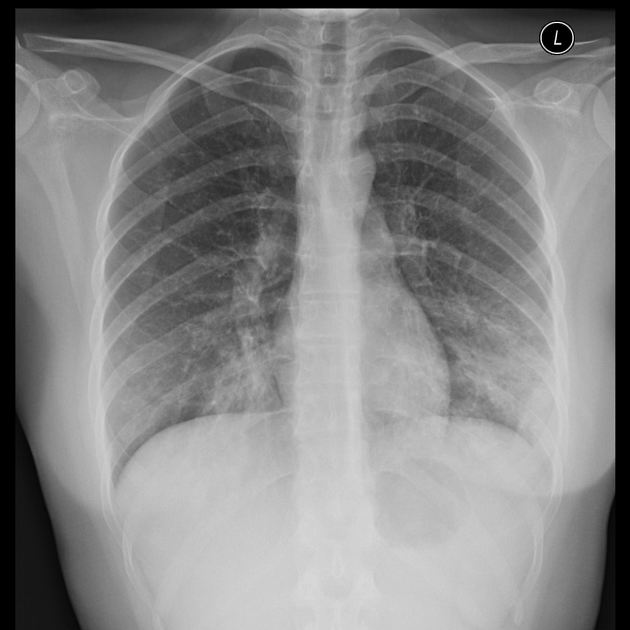

6. یافتههای رادیولوژیک

غیراختصاصی

قابل افتراق از پنومونی ویروسی یا باکتریال نیست

الگوهای ممکن:

اینفیلتراسیون منتشر دوطرفه

پنومونی لوبار

لنفادنوپاتی هیلار (تا ۳۰٪)

موارد نادر ولی مهم:

افیوژن پلورال بزرگ

پنومونی نکروزان

⟵ بیشتر در:نقص ایمنی

سندرم داون

بیماریهای مزمن قلبیریوی

کمخونی داسیشکل